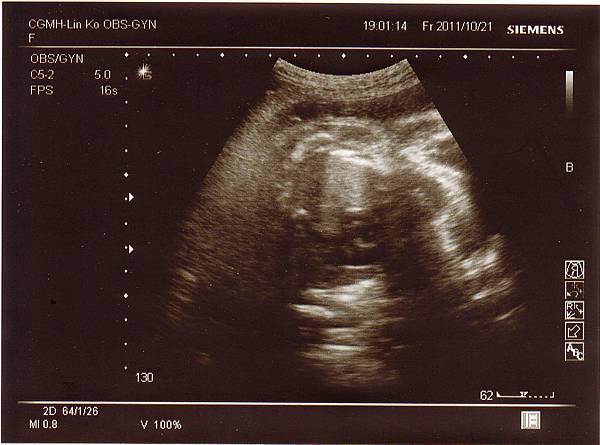

醫生說我的肚子真的不大,但寶寶的成長還是正常範圍,

比他想像中的好很多(原以為肚子太小寶寶也會很小),